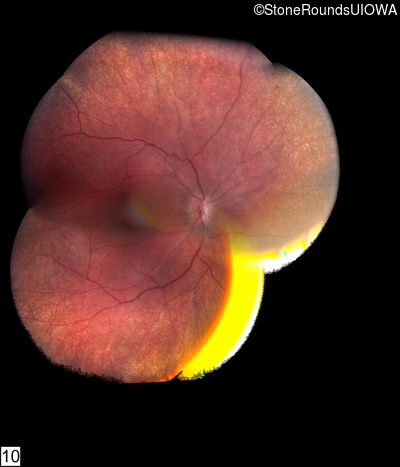

Fundus Montage - Right - No Light Perception

Exemplar